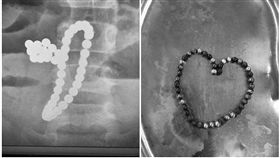

3歲女童吃什麼吐什麼 X光一照全「魚卵」

小孩在玩什麼都要相當注意!中國一名3歲女童出現嘔吐、...

女童肚子驚見「61顆白點」醫嘆一輩子毀了

俗稱「巴克球」的小型磁力珠在孩童之間流行,卻也發生多...

2歲童誤吞珠珠 腸壁竟出現詭異光圈

對於家中有幼兒的家庭來說,必須要花更多的時間與細心來...

29顆小珠珠塞下體 吸成一團醫嚇呆

中國一名男子日前因為血尿、尿痛的問題就醫,不過面對醫...

誤吞46顆磁力珠!串成手鍊腐蝕腸胃

買給小孩的玩具真的要多多注意,若不小心吃下肚,後果真...

誤吞磁力珠!男童胃部驚現「手環」

小小一顆磁力珠,號稱可以訓練幼童的腦部發展,不少家長...

7磁珠隔腸緊吸…童誤吞釀嚴重腸穿孔

大陸陝西一名3歲男童,日前誤吞7顆「磁力珠」導致劇烈...